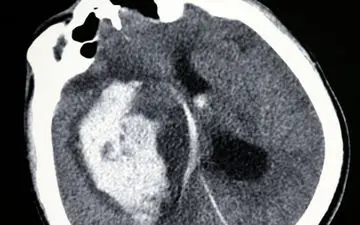

تومور مغزی یعنی رشد غیرطبیعی سلولها در مغز یا اطراف آن. میتونه خوشخیم (غیرسرطانی) باشه یا بدخیم (سرطانی). این…

انواع مختلفی از تومورهای مغزی وجود دارد. برخی سرطانی (بدخیم) و برخی غیرسرطانی (خوش خیم) هستند. برخی از تومورهای بدخیم…